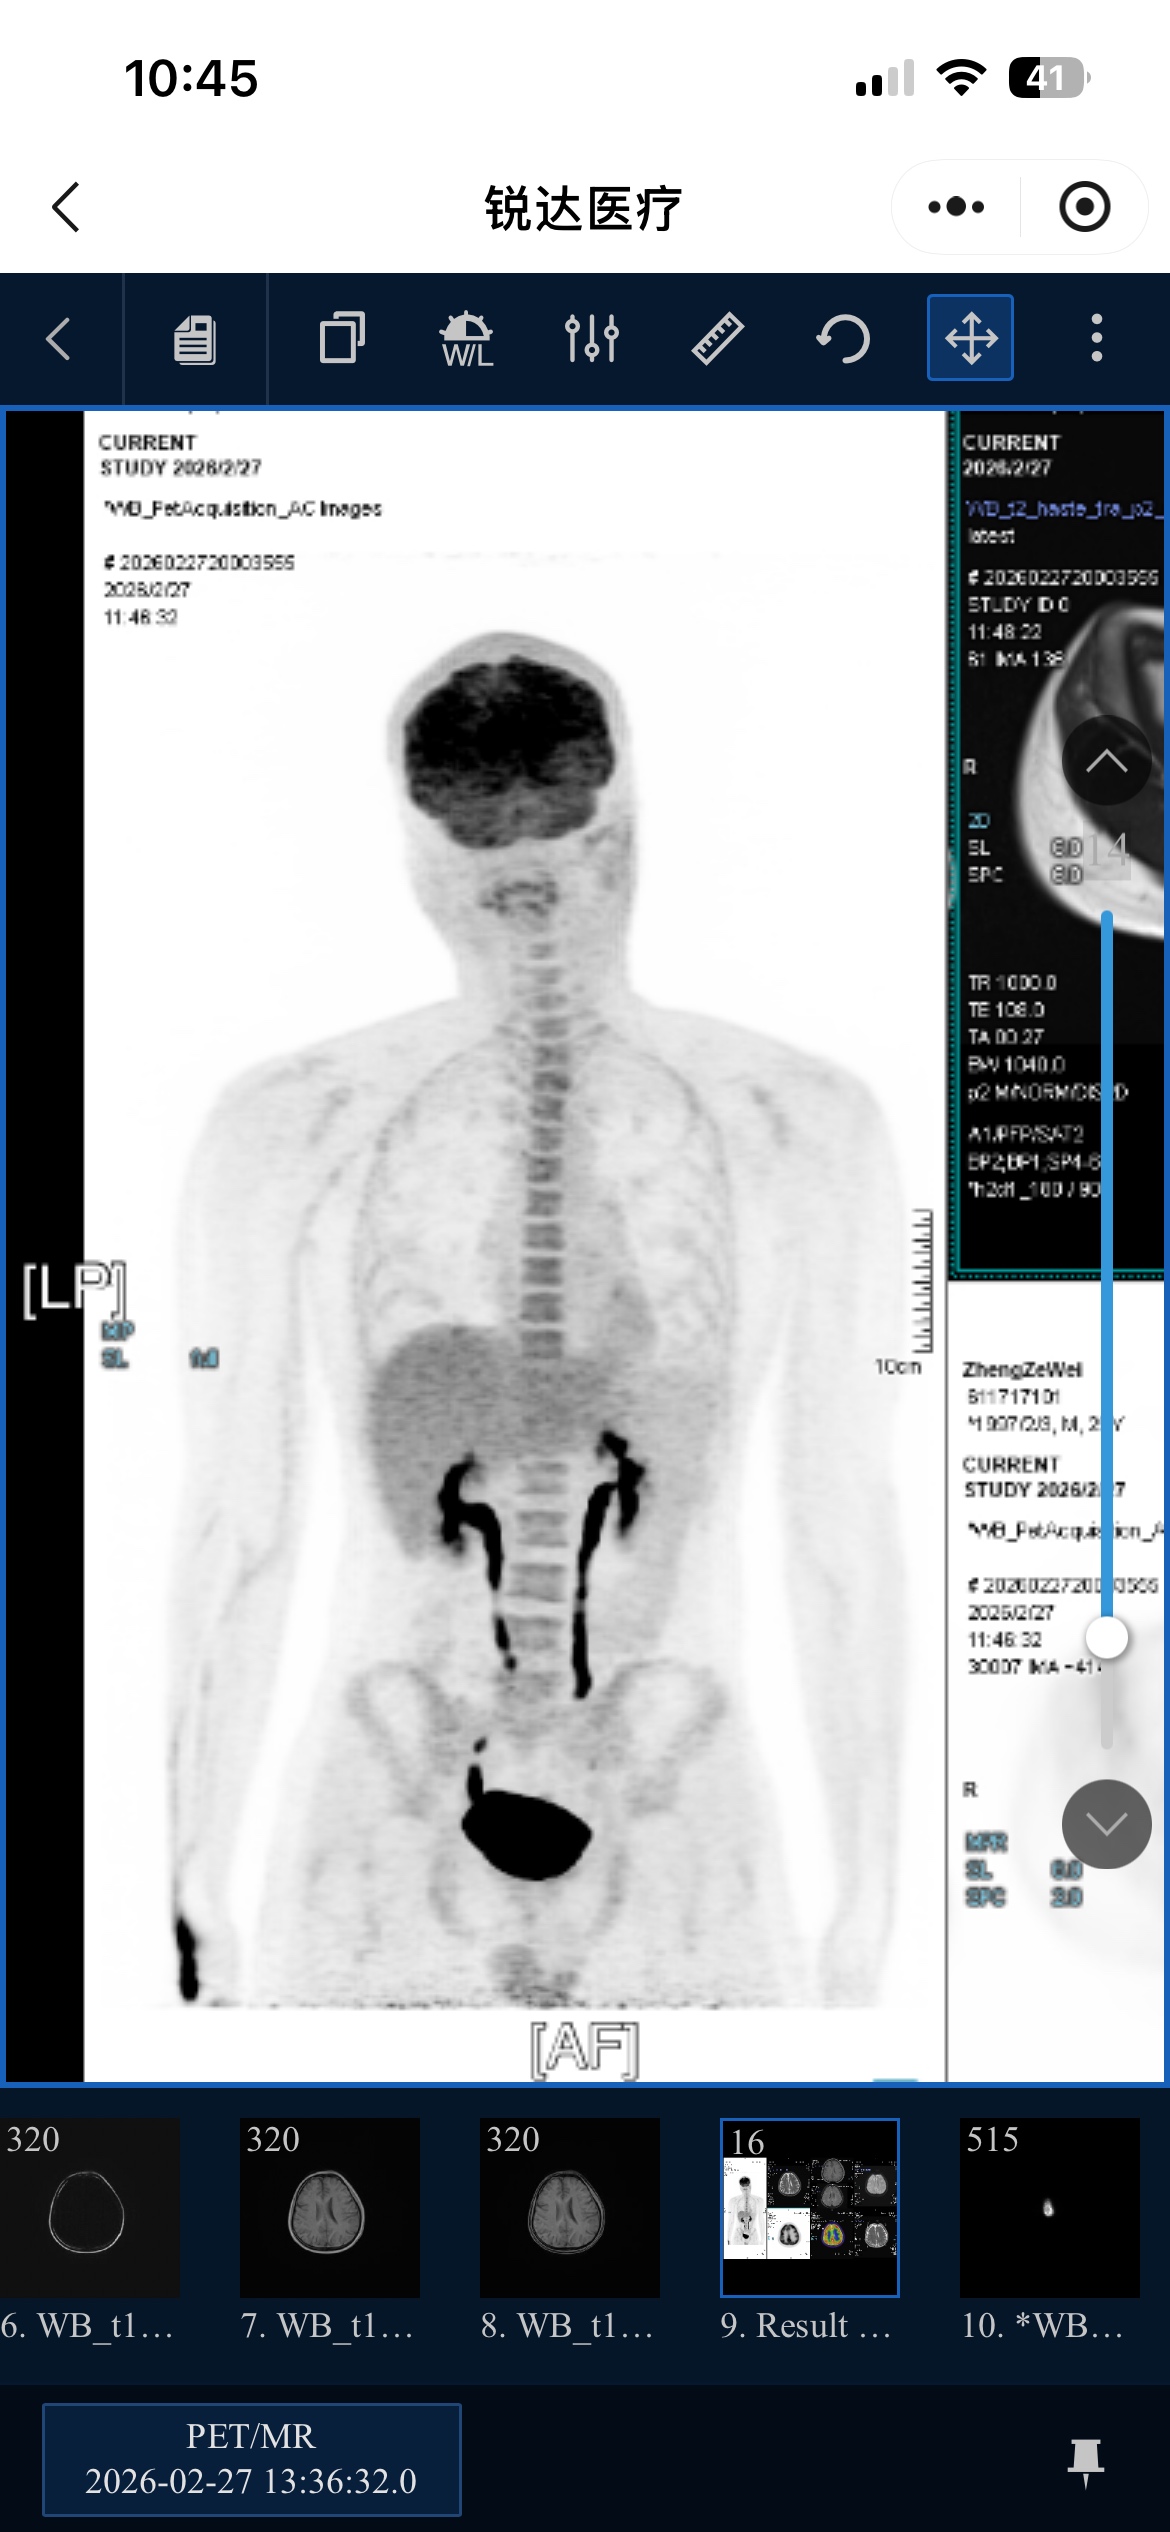

病理报告没出,各位大神能看一下我的pet ct报告可能是几级几期 ai分析说是1-2期,发病位置耳朵腮腺肿块已切除,切除后做的pet,有一个颈部淋巴结,ki-67 是4%